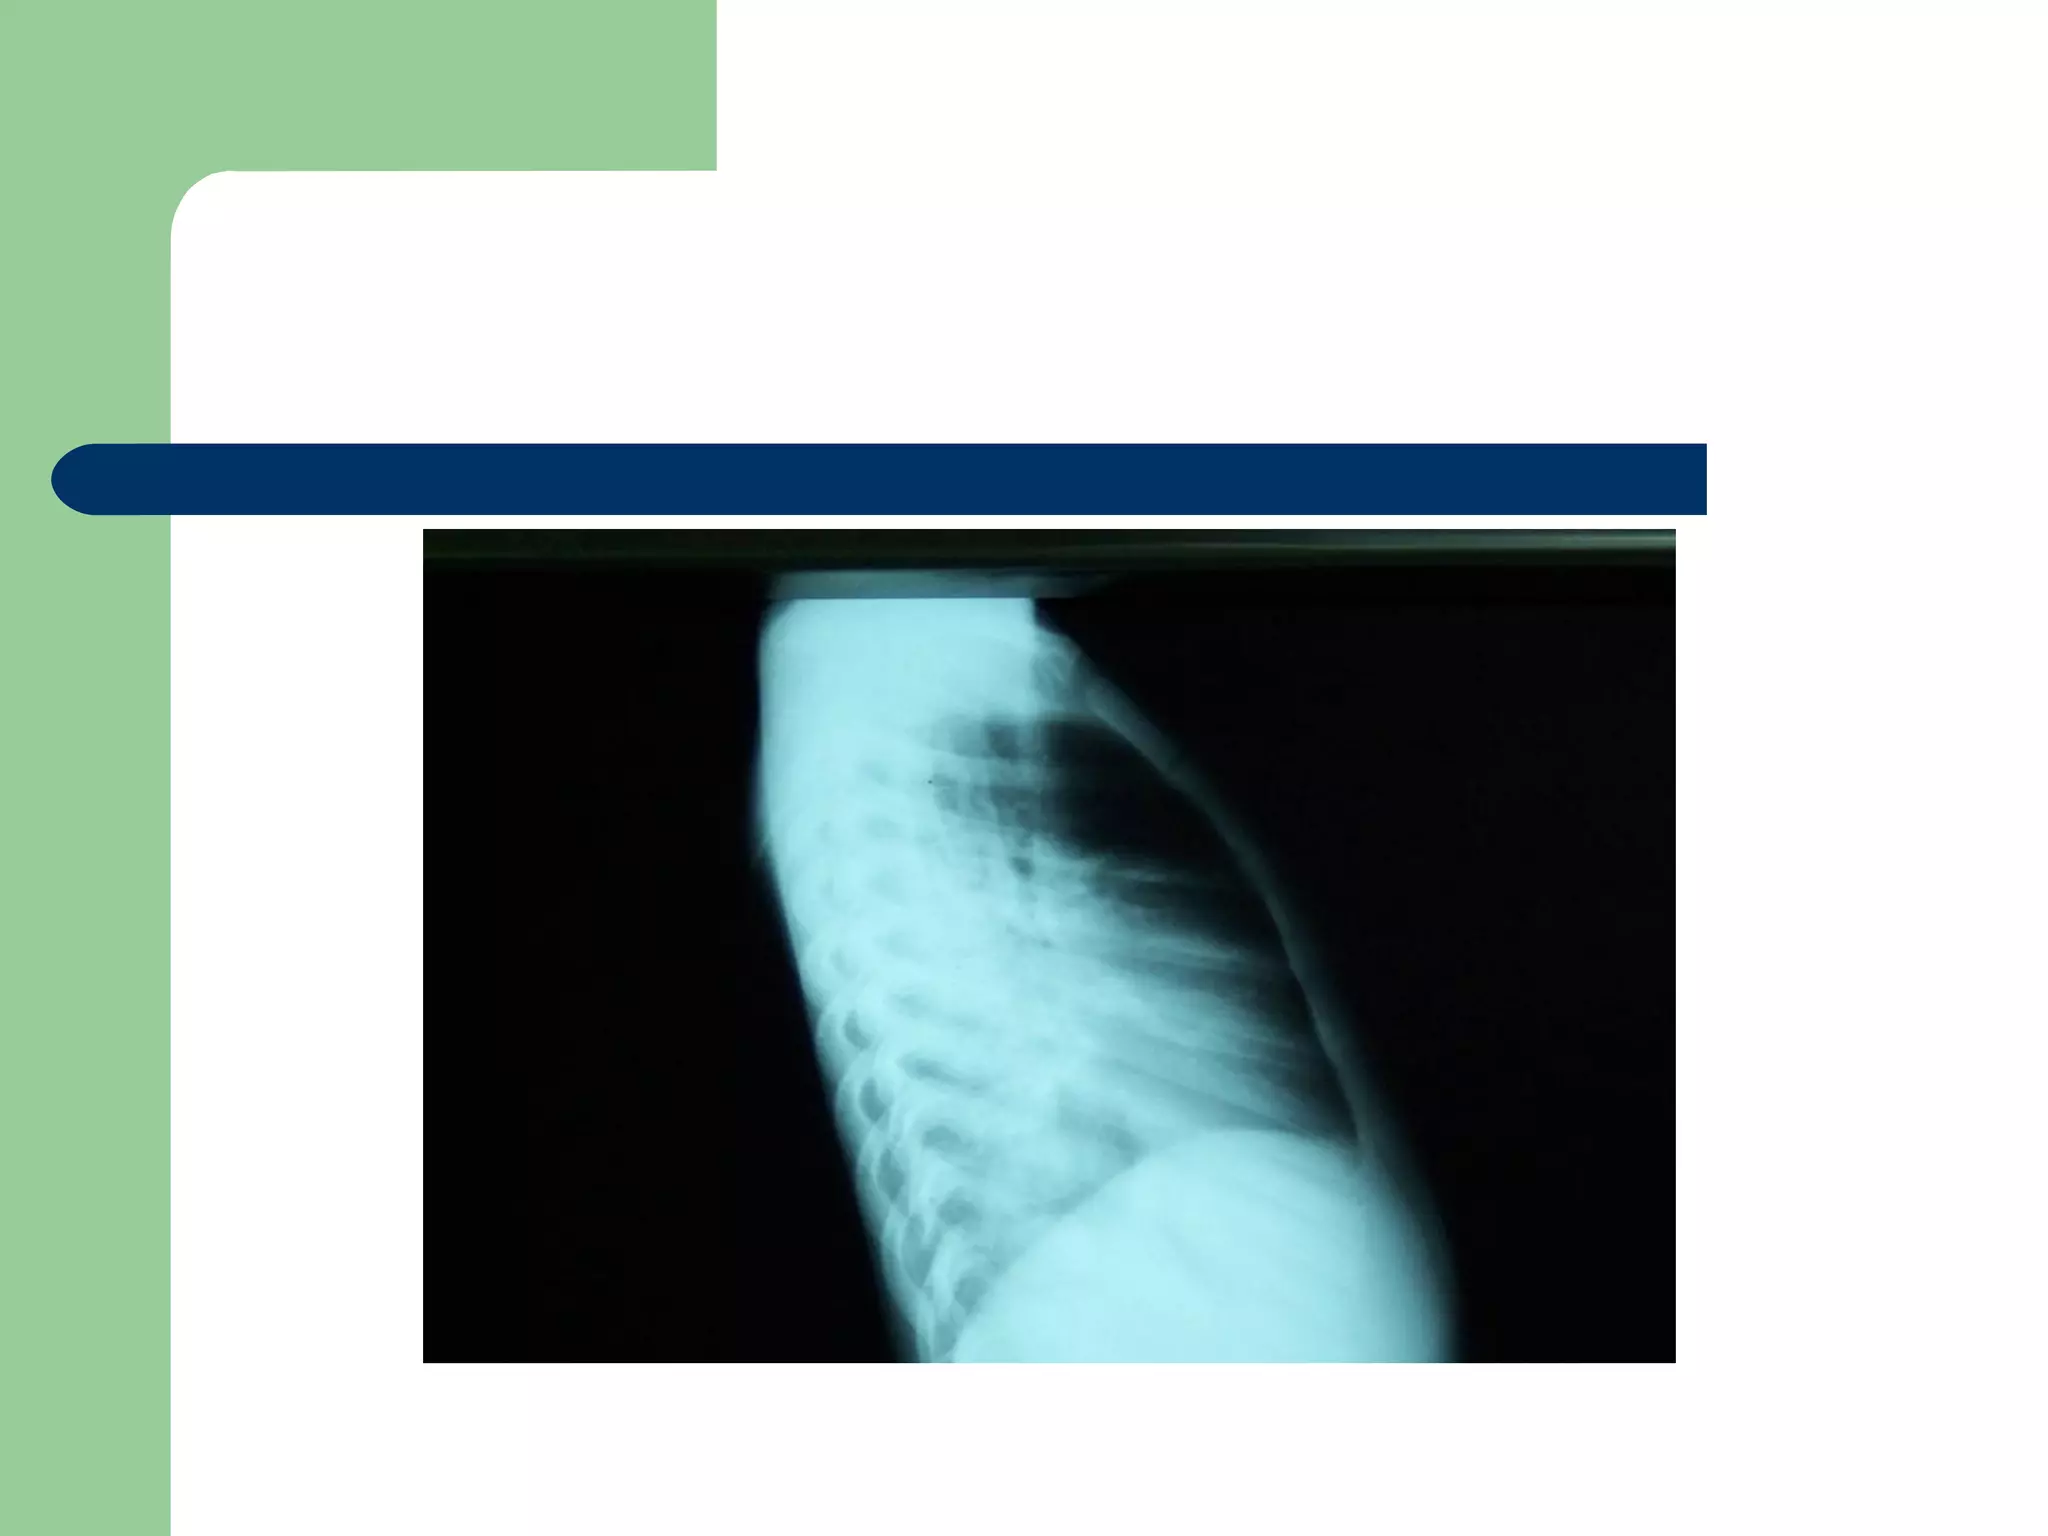

 CXR may be normal if the FB is not radio- opaque.

or it can show a radio- opaque FB such as bone.

Obstructive emphysema: is produced by intra-bronchial

FB that allows air to enter in inspiration and prevents its

exit in expiration.

Lung collapse (complete or partial) is produced by a FB

that blocks the bronchus completely.

Unresolved pneumonic consolidation.

A five and a half yr old boy: non-resolved cough

Of 40 days duration

DIAGNOSIS…  Examination:signs of respiratory distress may be present.  CXR may be normal if the FB is not radio- opaque. or it can show a radio- opaque FB such as bone. Obstructive emphysema: is produced by intra-bronchial FB that allows air to enter in inspiration and prevents its exit in expiration. Lung collapse (complete or partial) is produced by a FB that blocks the bronchus completely. Unresolved pneumonic consolidation. Lung abscess or broncheictasis are caused by a long-standing FB.

A five anda half yr old boy: non-resolved cough Of 40 days duration